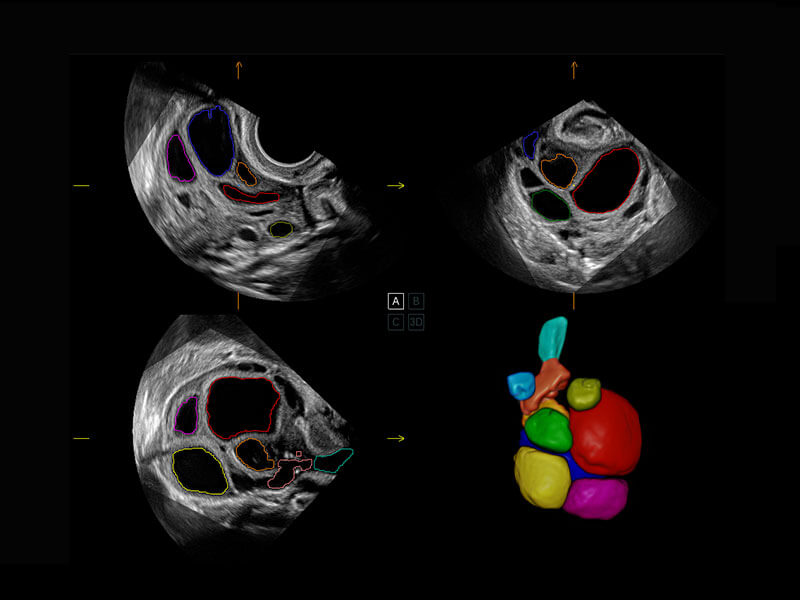

P60搭载一系列胎儿心脏成像技术,实现精细的胎儿心脏评估。

四腔切面

胎心容积成像